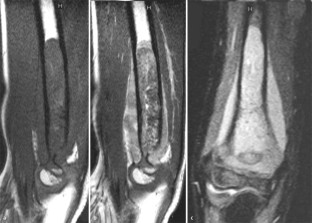

MRI morphology of bone tumors and tumor-like lesions

Für das Staging und die Charakterisierung von Knochentumoren und tumorähnlichen Läsionen ist in der Magnetresonanztomographie (MRT) der Einsatz von Spinechosequenzen erforderlich. Die MRT hat nur einen geringen Stellenwert in der Bestimmung der Dignität. Obwohl viele Knochentumoren und tumorähnliche Läsionen eine vergleichbare Morphologie in dieser bildgebenden Modalität aufweisen, können einige Tumorentitäten mittels MRT recht zuverlässig diagnostiziert werden. Hierzu zählen Knorpeltumoren, die solitäre und aneurysmatische Knochenzyste, der Riesenzelltumor, fetthaltige Läsionen und bis zu einem gewissen Grad auch das Osteoidosteom und das Osteoblastom. Es werden praktische Tipps gegeben, wann bei Tumorverdacht die MRT eingesetzt werden sollte, wie bei einem zufällig bei einer MRT gefundenen Tumor die Untersuchung modifiziert werden sollte und welcher Tumor vorliegen könnte.

Spin-echo sequences are mandatory at MRI for staging and characterization of bone tumors and tumor-like lesions. MRI is of minor value in the estimation of the malignant potential of an osseous lesion. Although many bone tumors and tumor-like lesions present similar morphology at MRI, some entities can be diagnosed with good reliability. These include chondrogenic tumors, solitary and aneurysmal bone cysts, giant cell tumors, lesions containing fatty tissue and, to a certain extent, osteoid-osteomas and osteoblastomas. Practical advice is given regarding when to perform a MRI study in cases of tumor suspicion. Further advices are given for cases a tumor is found incidentally at a MRI study, how to modify the study and which kind of tumor may be present.